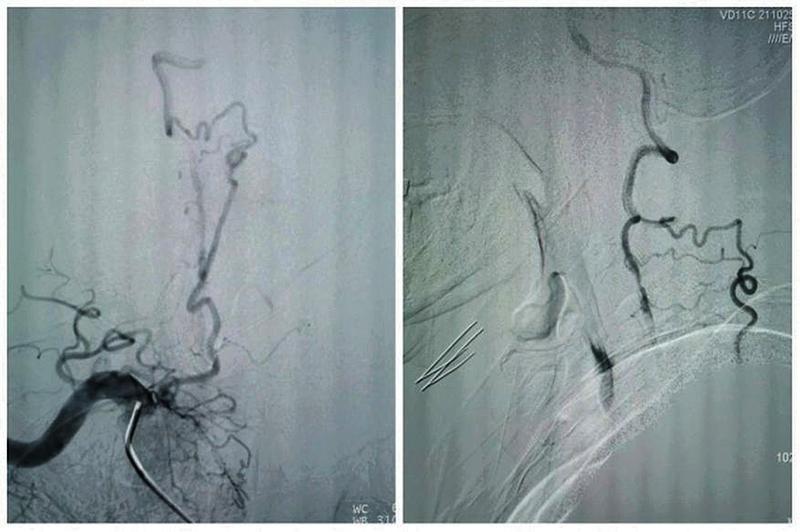

患者拜某,男,65岁,因反复头晕、晕厥1年,加重10天入院,既往5年前因心肌梗死在外院冠脉植入5枚支架。本次发病后当地医院发现患者脑后部的主干动脉——双侧椎动脉在颈部完全闭塞,当地医院药物医治无效,患者慕名从商洛来到我院神经内科。入院后经过脑血管造影发现患者双侧椎动脉颈部闭塞段大约10cm,闭塞远端经过甲状颈干及肋颈干向V2近颅底以远代偿供血,但因代偿不足,患者近来反复脑梗死2次,此次入院再次提示小脑新鲜脑梗死。

最终,在患者入院第4天,张桂莲教授带领的介入团队选择局麻条件下为患者成功实施了神经介入领域的高难度手术—左侧无残端椎动脉长节段慢性闭塞再通术。因术前清晰的影像显影及准确的体外定位标记,左侧优势椎动脉顺利开通,手术耗时仅仅约90分钟。术中及术后患者配合良好,无任何不适。出院前复查头颈一体化超声提示左侧椎动脉支架位置良好,血流通畅,颅内血流速度及频谱未见明显异常。充分向患者及家属告知出院注意事项及复查时间后,目前该患者已顺利出院。